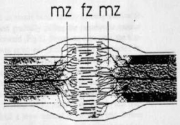

| 08:48, 18 ביוני 2013 | איטומי חריצים1.png (קובץ) |  |

194 קילו־בייטים | Motyk | 1 | |